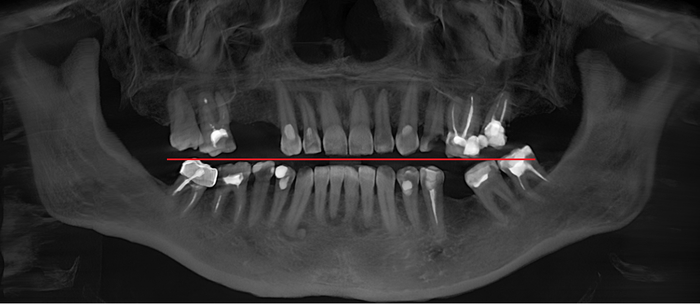

Ниже панорамный снимок, где хорошо видно, как из-за длительного (овер 10 лет) отсутствия 6-го зуба на нижней челюсти слева (на снимке справа) соседние зубы – седьмой и восьмой – наклонились в сторону отсутствующего.

Если посмотреть внимательно, то можно обратить внимание на то, что седьмой и восьмой зубы стоят в зубном ряду выше, чем с противоположной стороны:

Конечно, эта линия очень условна. Я лишь хотел, чтобы эта проблема явно бросилась в глаза.